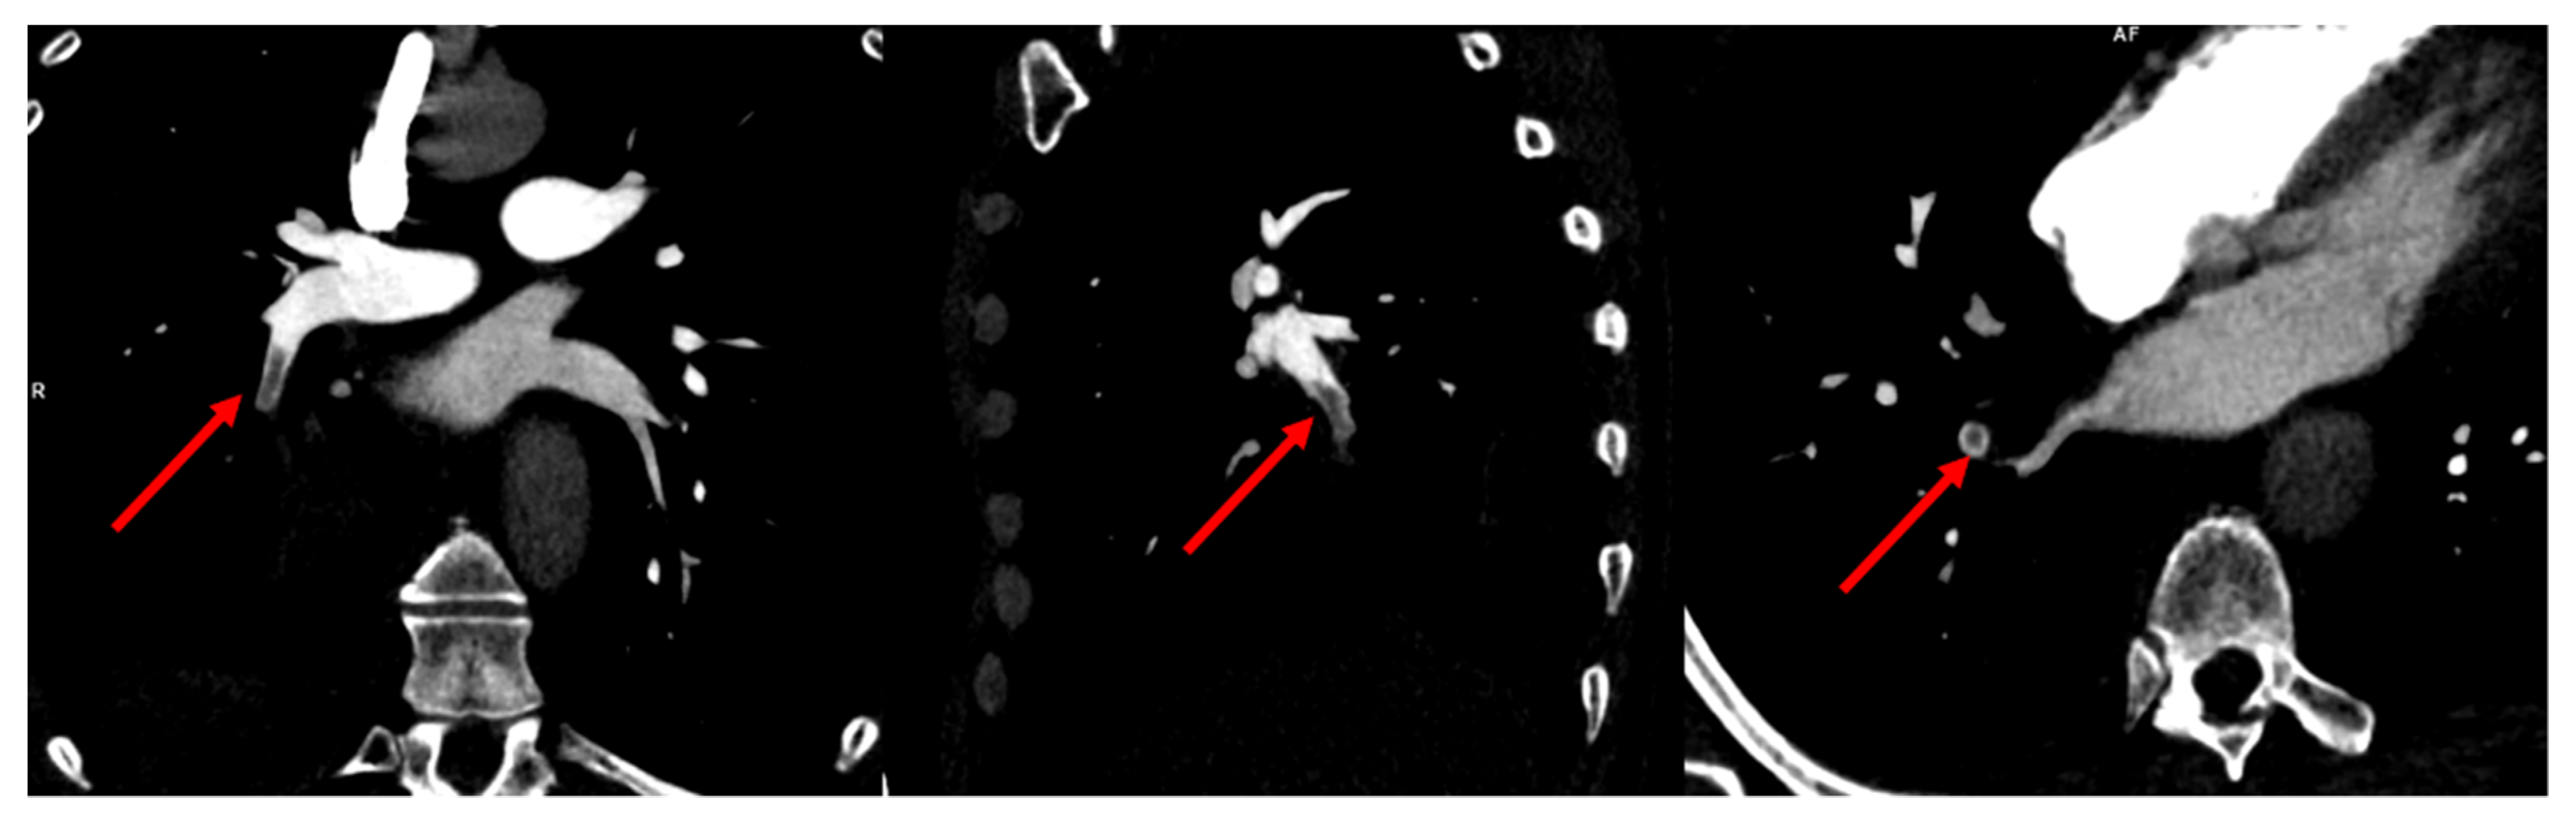

2. Case Presentation